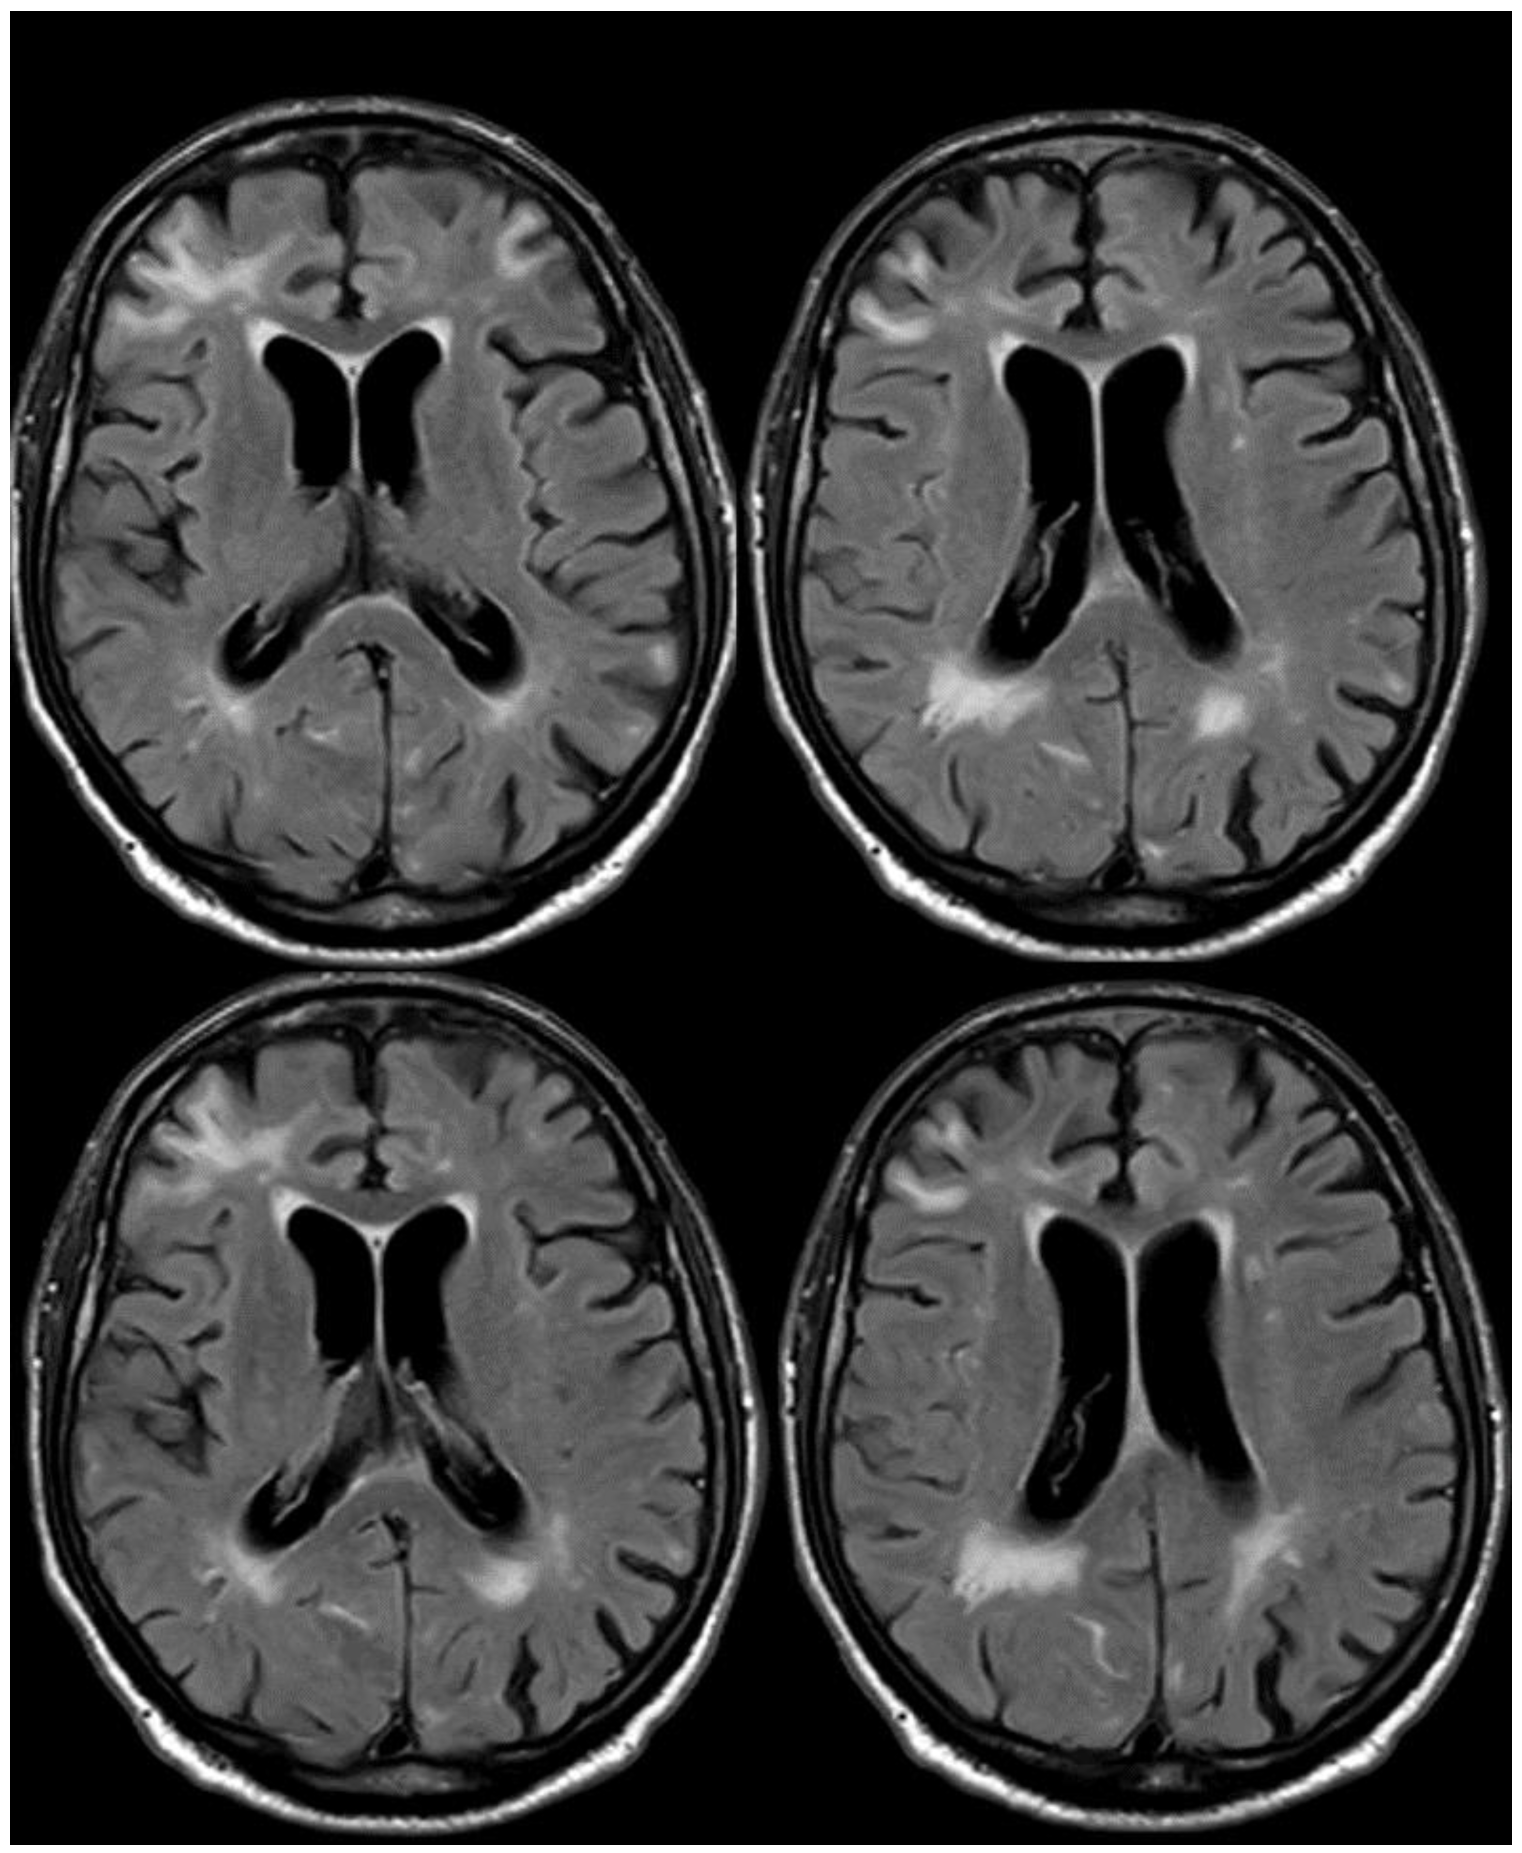

3. May 2014: CAA-Related Inflammation